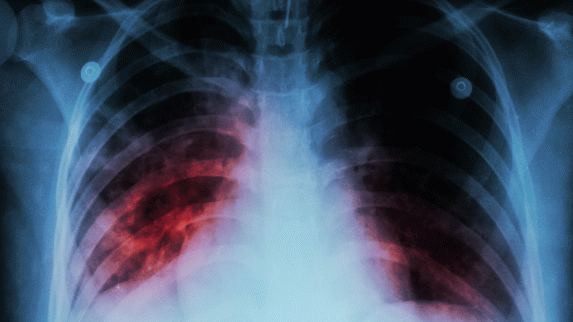

Rutgers to Lead Consortium of Seven Universities and Eight Nations to Curb Tuberculosis

Rutgers New Jersey Medical School will coordinate a worldwide effort to stop one of the deadliest infectious diseases from spreading with a $20 million grant over five years from the National Institute of Allergy and Infectious Diseases (NIAID).